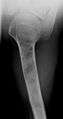

On radiographs, streaks of low density are seen projecting through the diaphyses into the epiphyses of the long bones, due to ectopic cartilage deposits. With age, the cartilage may calcify in the typical "snowflake" pattern.

X-ray showing enchondromas localized in the lower part of the radius of a 37-year-old patient affected with Ollier disease